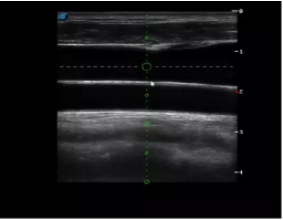

多數的生殖科醫(yī)生對于受精卵的植入采用憑經驗操作或是使用傳統(tǒng)腔內探頭引導,同樣存在手術空間小、受精卵放置位置不確定等風險。專業(yè)的宮腔專用探頭,配合專用的窺器使用,為醫(yī)生提供最大的手術視野。

胎移植臨床圖